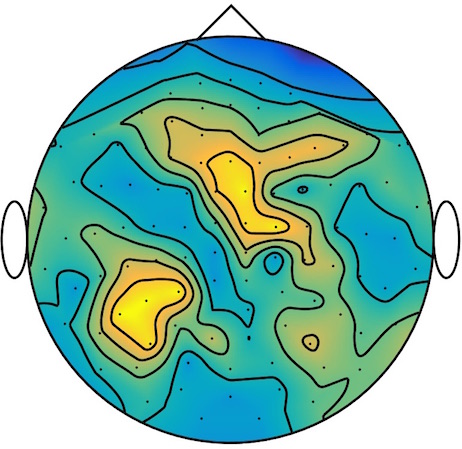

We applied our method to a magnetoencephalography (MEG) dataset. In this setup, brain activity of a subject is recorded (Elekta Neuromag, 306 sensors of which 204 planar gradiometers and 102 magnetometers, sampling frequency 1000Hz) while the subject reacted to the presentation of a target stimulus by pressing either the left or the right button.

Data is preprocessed applying signal space separation correction, interpolation of noisy sensors, and realignment of data into a subject-specific head position (MaxFilter, Elekta Neuromag). The signal was then filtered (low pass 40HZ), and artifacts such as blinks and heartbeats removed thanks to Signal-Space Projection using the Brainstorm software222http://neuroimage.usc.edu/brainstorm. The samples we used for our barycenter computations are an average of the norm of the two gradiometers for each channel from stimulation onto 50ms and the classes were left or right button.

| Class 1 | Class 2 | ||||||

|

|

|

|

|

|

|

|

| Sample 1 | Sample 2 | Sample 3 | Mean | Sample 1 | Sample 2 | Sample 3 | Mean |

|

|

|

|

|

|

|

|

This results in two classes of recordings, one for each pressed button. We aim at computing a representative activity map for each class using Wasserstein barycenters. For each class we have recordings each having samples located on the vertices of an hexahedral mesh of a hemisphere (corresponding to a MEG recording helmet). These recorded values are positive by construction, and we rescale them linearly to impose . Figure 6, top row, shows some samples from this dataset, displayed using interpolated colors as well as iso-level curves. The black dots represent the position of the electrodes on the half-sphere of the helmet, flattened on a 2-D disk.

We computed TV-regularized barycenters independently for each class by solving (16) with the TV regularization using the projected gradient descent method (22). We used a squared Euclidean metric (24) on the flattened hemisphere. Since the data is defined on an irregular graph, instead of (23), we use a graph-based discrete gradient. We denote the graph which connects neighboring electrodes. The gradient operator on the graph is

The total variation on this graph is then obtained by using , the norm, i.e. we use in (23).

Figure 6 compares the naive barycenters (i.e. the usual mean), barycenters obtained without regularization (i.e. ) and barycenters computed with an increasing regularization strength . The input histograms being very noisy, the use of regularization is important to make the area of significant activity emerge from the noise. The use of a TV regularization helps to keep a sharp transition between active and non-active regions.